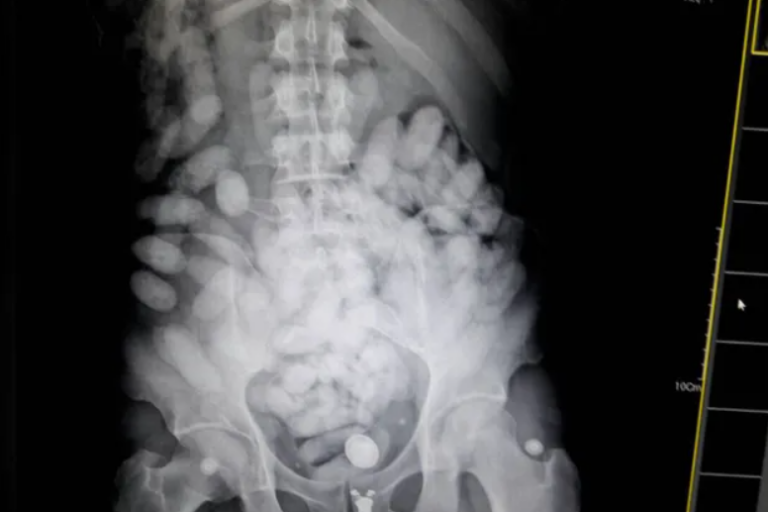

Aos policiais bolivianos que a atenderam, ela confessou ter ingerido 73 cápsulas da droga para poder entrar no Brasil com o produto e, como estava passando mal, suspeitava que poderia ter havido um acidente pelo estouro de uma delas e que temia morrer por overdose.

Médicos do Instituto de Gastroenterologia do Hospital Japonês de Cochabamba atenderam a paciente e exames radiológicos confirmaram a ingestão das cápsulas.